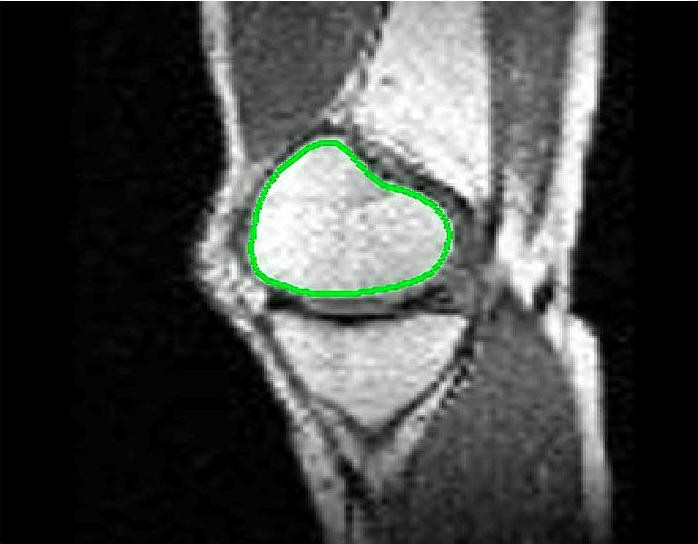

Test Images. We will perform initial tests on the images shown in Figs. 5–7. We have provided the ground truth and initialisation used for each image. Test Images 1–3 are synthetic, Test Image 4 is an MRI scan of a knee, Test Images 5–6 are abdominal CT scans, and Test Images 7–9 are lung CT scans. They have been selected to present challenges relevant to the discussion in §2. We focus on medical images as this is the application of most interest to our work. In the following we will discuss the results in terms of synthetic images (1–3) and real images (4–9). We also test the proposed approach on a larger data set of 30 CT images (a sample of which is presented in Fig. 18), comparing against existing selective methods detailed in §3.

Real Images. In Fig 12 we present results for Test Images 4–6. Here, the proposed model performs in a similar way to its competitors because these images are more typical selective segmentation problems in the sense that there is a clear distinction between the foreground and background intensities. In particular, the values in each case are: Test Image 4 , Test Image 5 , and Test Image 6 . It can be seen that the proposed model is competitive compared to previous approaches. The performance is quite poor for Test Image 5, but is arguably still the best for this challenging case. In Fig. 13 we present results for Test Images 7–9. Here the proposed model outperforms previous approaches significantly for each image. This is mainly due to the type of image considered. Specifically, the true intensities are: Test Image 7 , Test Image 8 , and Test Image 9 . The proposed model is capable of achieving results where , with other models failing completely in these cases.

Here we aim to address the question of whether each model is capable of achieving an accurate result. In other words, assuming that factors such as parameter and user input sensitivity are ignored, how successful is each approach. In Table 1 we present the optimal TC values for each model found from the tests described in the previous section, with the highest value in bold. We include values for CAC Nguyen:12 and SRW SRW , which we have obtained by iteratively refining the user input and running the algorithm. It is worth mentioning that we are using the authors’ implementation of each method. For each image, the results presented in Table 1 are the most accurate we could obtain given a reasonable level of input (comparisons with identical input are discussed in §7.4). Immediately we can see that the proposed model consistently outperforms the other models in terms of accuracy for the test images (RSF equals it for Test Image 1, SRW equals it for Test Images 1-3, and beats it for Test Image 8). Below we will discuss some relevant details of the results, again by splitting the test images into synthetic and real.

Real Images. In Table 1 we can see that the proposed model is the most successful in terms of optimal accuracy. It is worth noting some inconsistency in the other models, with all but GAV having results that fall below TC for at least one image. GAV performs well for Test Images 4–9, with the proposed model slightly outperforming it in each case. It is worth reminding the reader that for GAV the parameters have been refined for each example. Fixing this results in more variability in the quality of results. The proposed model has no such parameter optimisation between examples. CAC and SRW perform reasonably well for these images, although are sometimes substandard for Test Images 4-7. This is despite extensive refinement of the user input to achieve an acceptable result. We present the optimal results for Test Image 9 in Fig. 14. Here we can see how much variation there is in the quality of results for this lung CT image. CAC and SRW are competitive in this instance. Of the remaining approaches GAV is the most competitive (TC ), but is visually inadequate. Two other models (CV, HYB) fail completely. In this case, the problem looks quite straightforward and yet other fitting terms are insufficient to produce a good result. Again, the proposed model tends to be superior in cases where and is capable of achieving very good results for all the images considered. This highlight the advantages of the proposed fitting term.